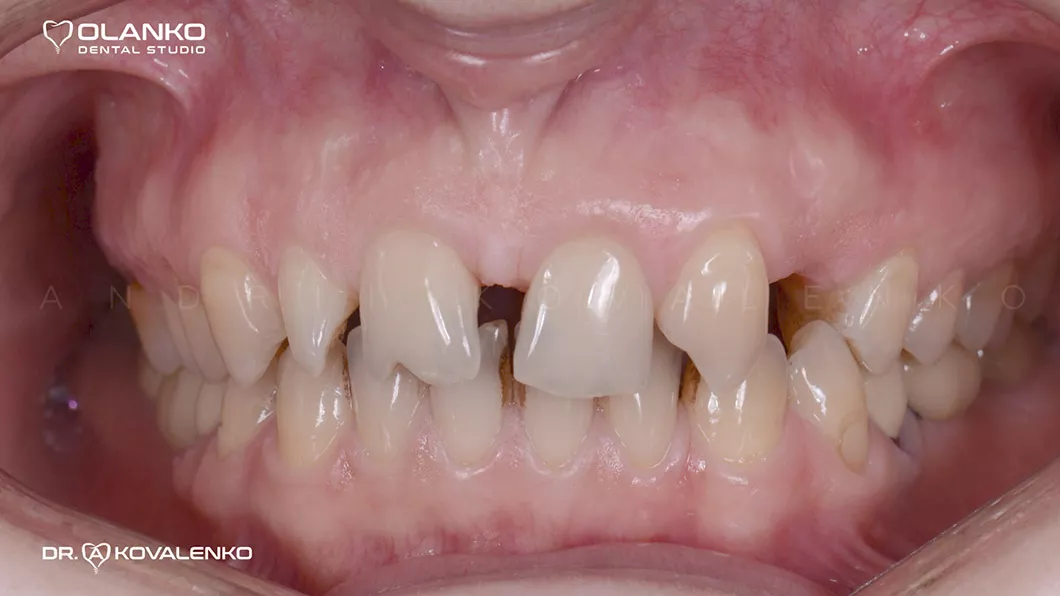

Пациентка обратилась с жалобами на неудовлетворительную эстетику, наличие промежутков между зубами (тремы, диастемы) полное отсутствие (адентия бокового резца слева).

Диагностика: эстетический анализ, создание проекта новой улыбки DSD (цифровой дизайн улыбки).

Лечение: замена старых несостоятельных композитных реставраций и лечение кариеса, повторное лечение каналов с использованием микроскопа в 3х зубах.

Установлен зубной имплантат в области 23 зуба.

Проведена хирургическая коррекция десневого контура в области фронтальных зубов.

Протезирование:12 керамических реставраций (коронки,виниры на зубах и имплантате) на верхней челюсти.

до